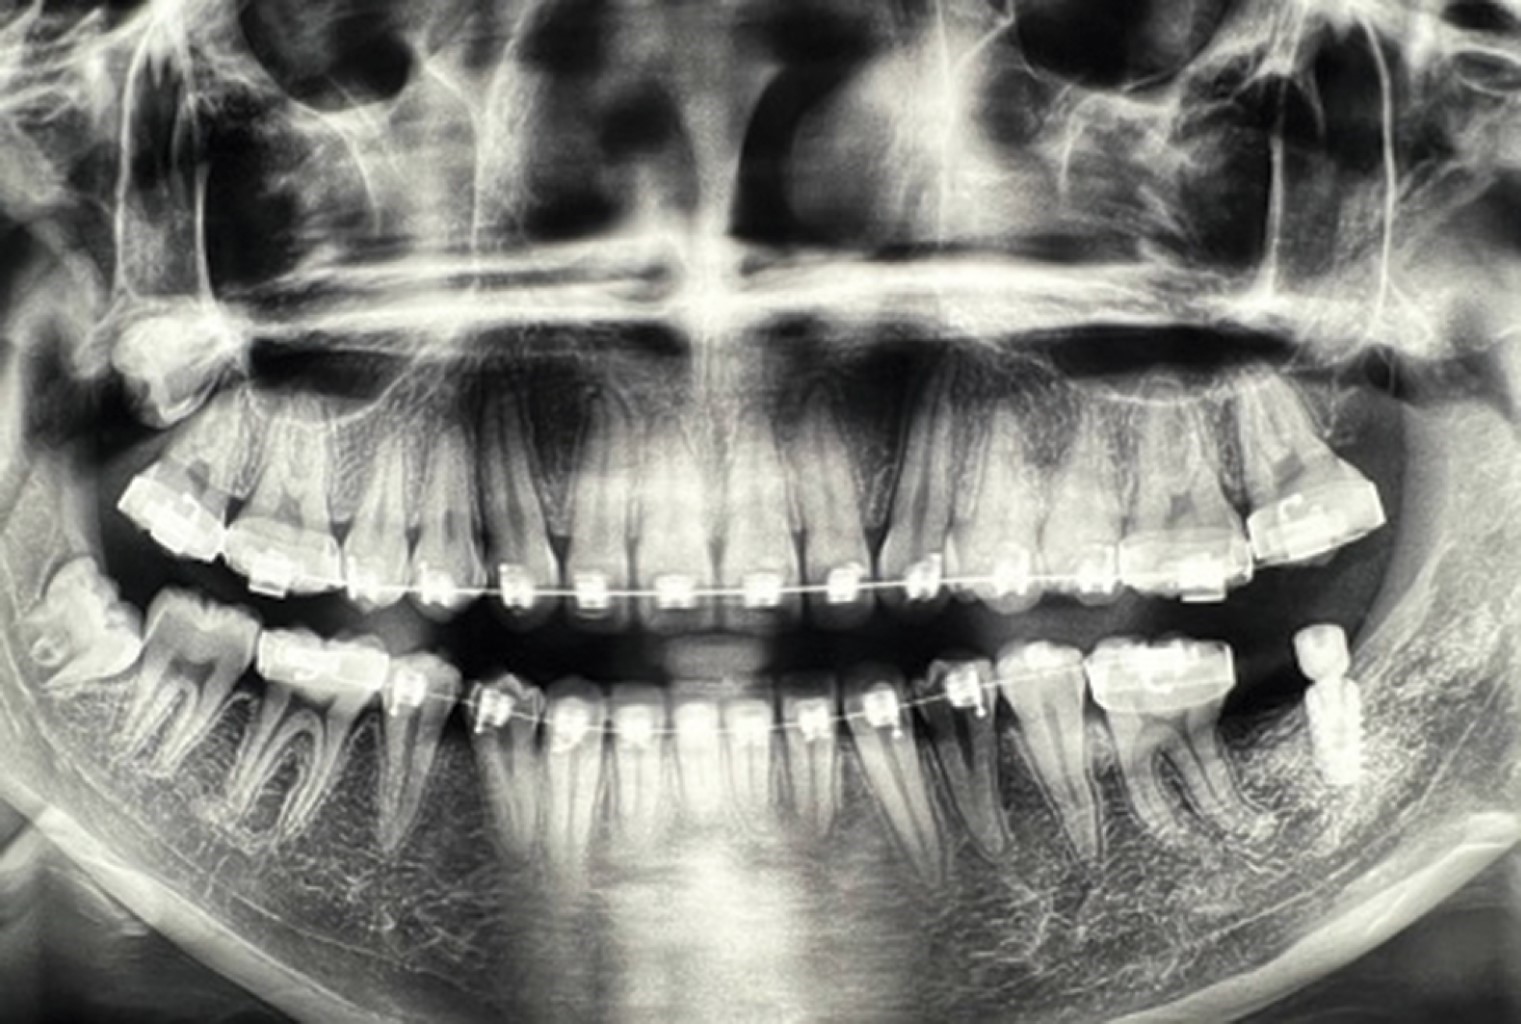

La radiografía panorámica permitió observar un área radiolúcida unilocular que se extendía a partir del cuerpo mandibular (Figura 1), desde la zona distal del primer molar inferior izquierdo hasta la parte mesial del segundo molar incluido, involucrando el canal del nervio inferior. El segundo molar inferior estaba incluido en la lesión y desplazado posterosuperiormente, así como desplazamiento basal del conducto dentario inferior. En la tomografía axial computarizada con reconstrucción se apreció una masa isodensa en el cuerpo y rama mandibular izquierda, con expansión de corticales vestibular y lingual (Figura 2).